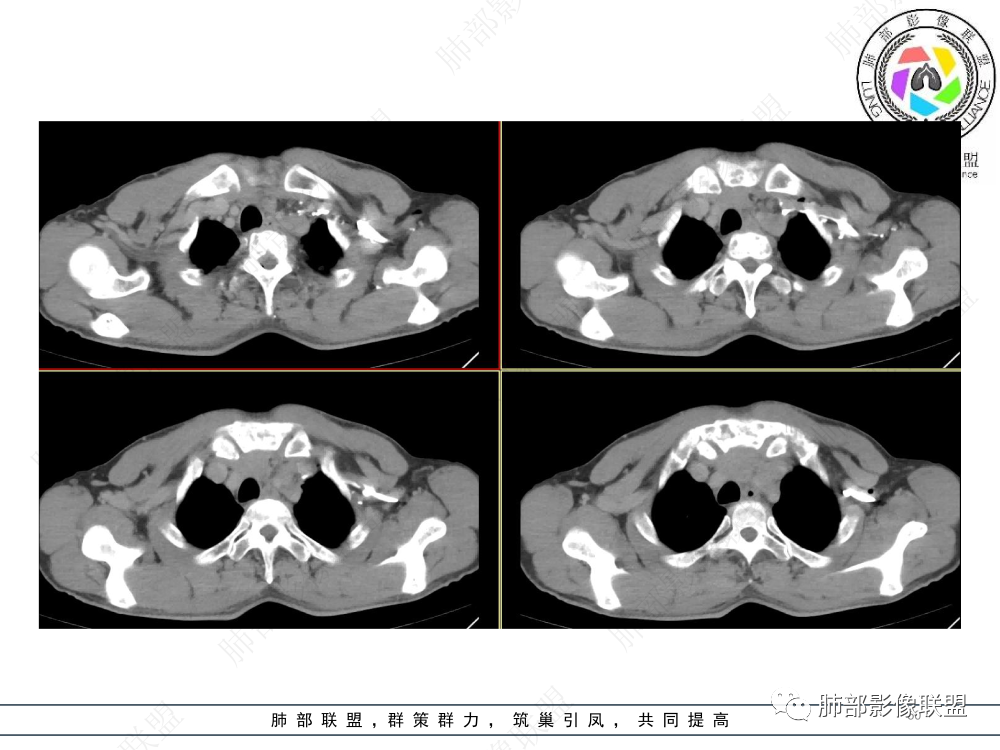

1.临床资料:中老年男性,病史较长-8个月,主诉胸痛,实验室资料:乳酸脱氢酶(LDH)升高。

2.影像表现:前上纵隔较大肿块,密度不均,形态不规则,边界不清,有结节样突起,脂肪间隙显示不清。病灶侵犯左无名静脉及上腔静脉,其中左无名静脉闭塞(胸背部侧支循环明显,亦表明回流受阻)。增强后轻中度不均强化。坏死边界欠清晰。可见心包积液,提示心包受侵犯。右侧上叶及纵隔胸膜下结节影,疑胸膜肺转移可能。胸骨柄后缘皮质不完整,疑骨质破坏(未提供骨窗及矢状位图像)。左锁骨上可见肿大淋巴结。